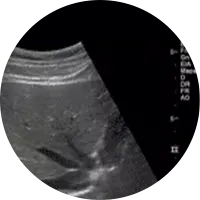

A Ecografia é um método de estudo e diagnóstico que permite, devido à emissão de ondas sonoras ou ultra-sons, examinar diversas áreas do corpo e órgãos e confirmar um diagnóstico clínico. Pode, portanto, ser usada para fins muito diversos como a observação ao pormenor do fígado, a vesícula biliar, rins, baço, tiróide, próstata, artérias e veias (Ecodoppler), entre outros. O exame de ecografia não causa nenhuma dor.

Existem vários tipos de preparação para os diferentes tipos de ecografia.